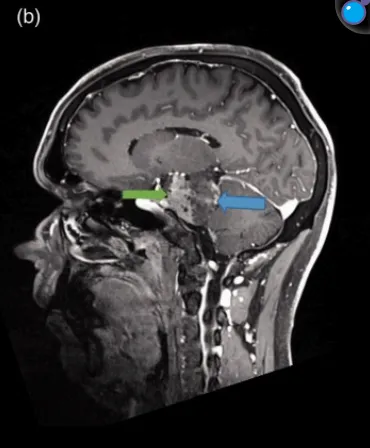

MR显示,肿瘤起源于天幕并向岩斜坡延伸,界限清晰,为轴外肿瘤,明显压迫脑干,瘤周无水肿,均匀增强强化,支持脑膜瘤的初步诊断。

从患者术前的影像中可以看出,肿瘤位置距离头皮远,术中需要穿过很深的正常脑组织以及相应血管,所以手术入路不清晰,很多情况下往往只切除一点。加上手术难度极大,很可能发生切除率较低,甚至是术中出血而提前终止手术的情况。即使手术做了,也可能造成偏瘫等严重的不可逆的神经损伤,使患者终身遭受手术后遗症的困扰。在岩斜区脑瘤的死亡率和致残率如此之高的情况下,选择适当的个体化治疗方案就更加重要了。